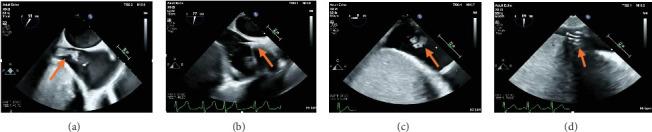

重复使用AngioVac清除延伸至肝静脉的巨大右心房血栓。

Repeat AngioVac Debulking of a Large Right Atrial Thrombus With Extension From the Hepatic Vein.

The AngioVac mechanical aspiration system has emerged in the literature as a viable treatment option for patients with intracardiac masses and thrombi and who are deemed high risk for cardiac surgery. Notably, it has been shown to be an effective treatment modality for the debulking of thrombi in the setting of malignancy. We present a case of repeat AngioVac debulking of a large right atrial thrombus with extension from the hepatic vein in the setting of advanced malignancy complicated by endocarditis.

摘要

血管内真空机械抽吸系统在文献中已成为心内肿块和血栓患者以及被认为心脏手术高风险患者的一种可行治疗选择。值得注意的是,它已被证明是在恶性肿瘤情况下清除血栓的有效治疗方式。我们报告一例在晚期恶性肿瘤合并心内膜炎的情况下,对从肝静脉延伸而来的巨大右心房血栓进行重复血管内真空清除术的病例。